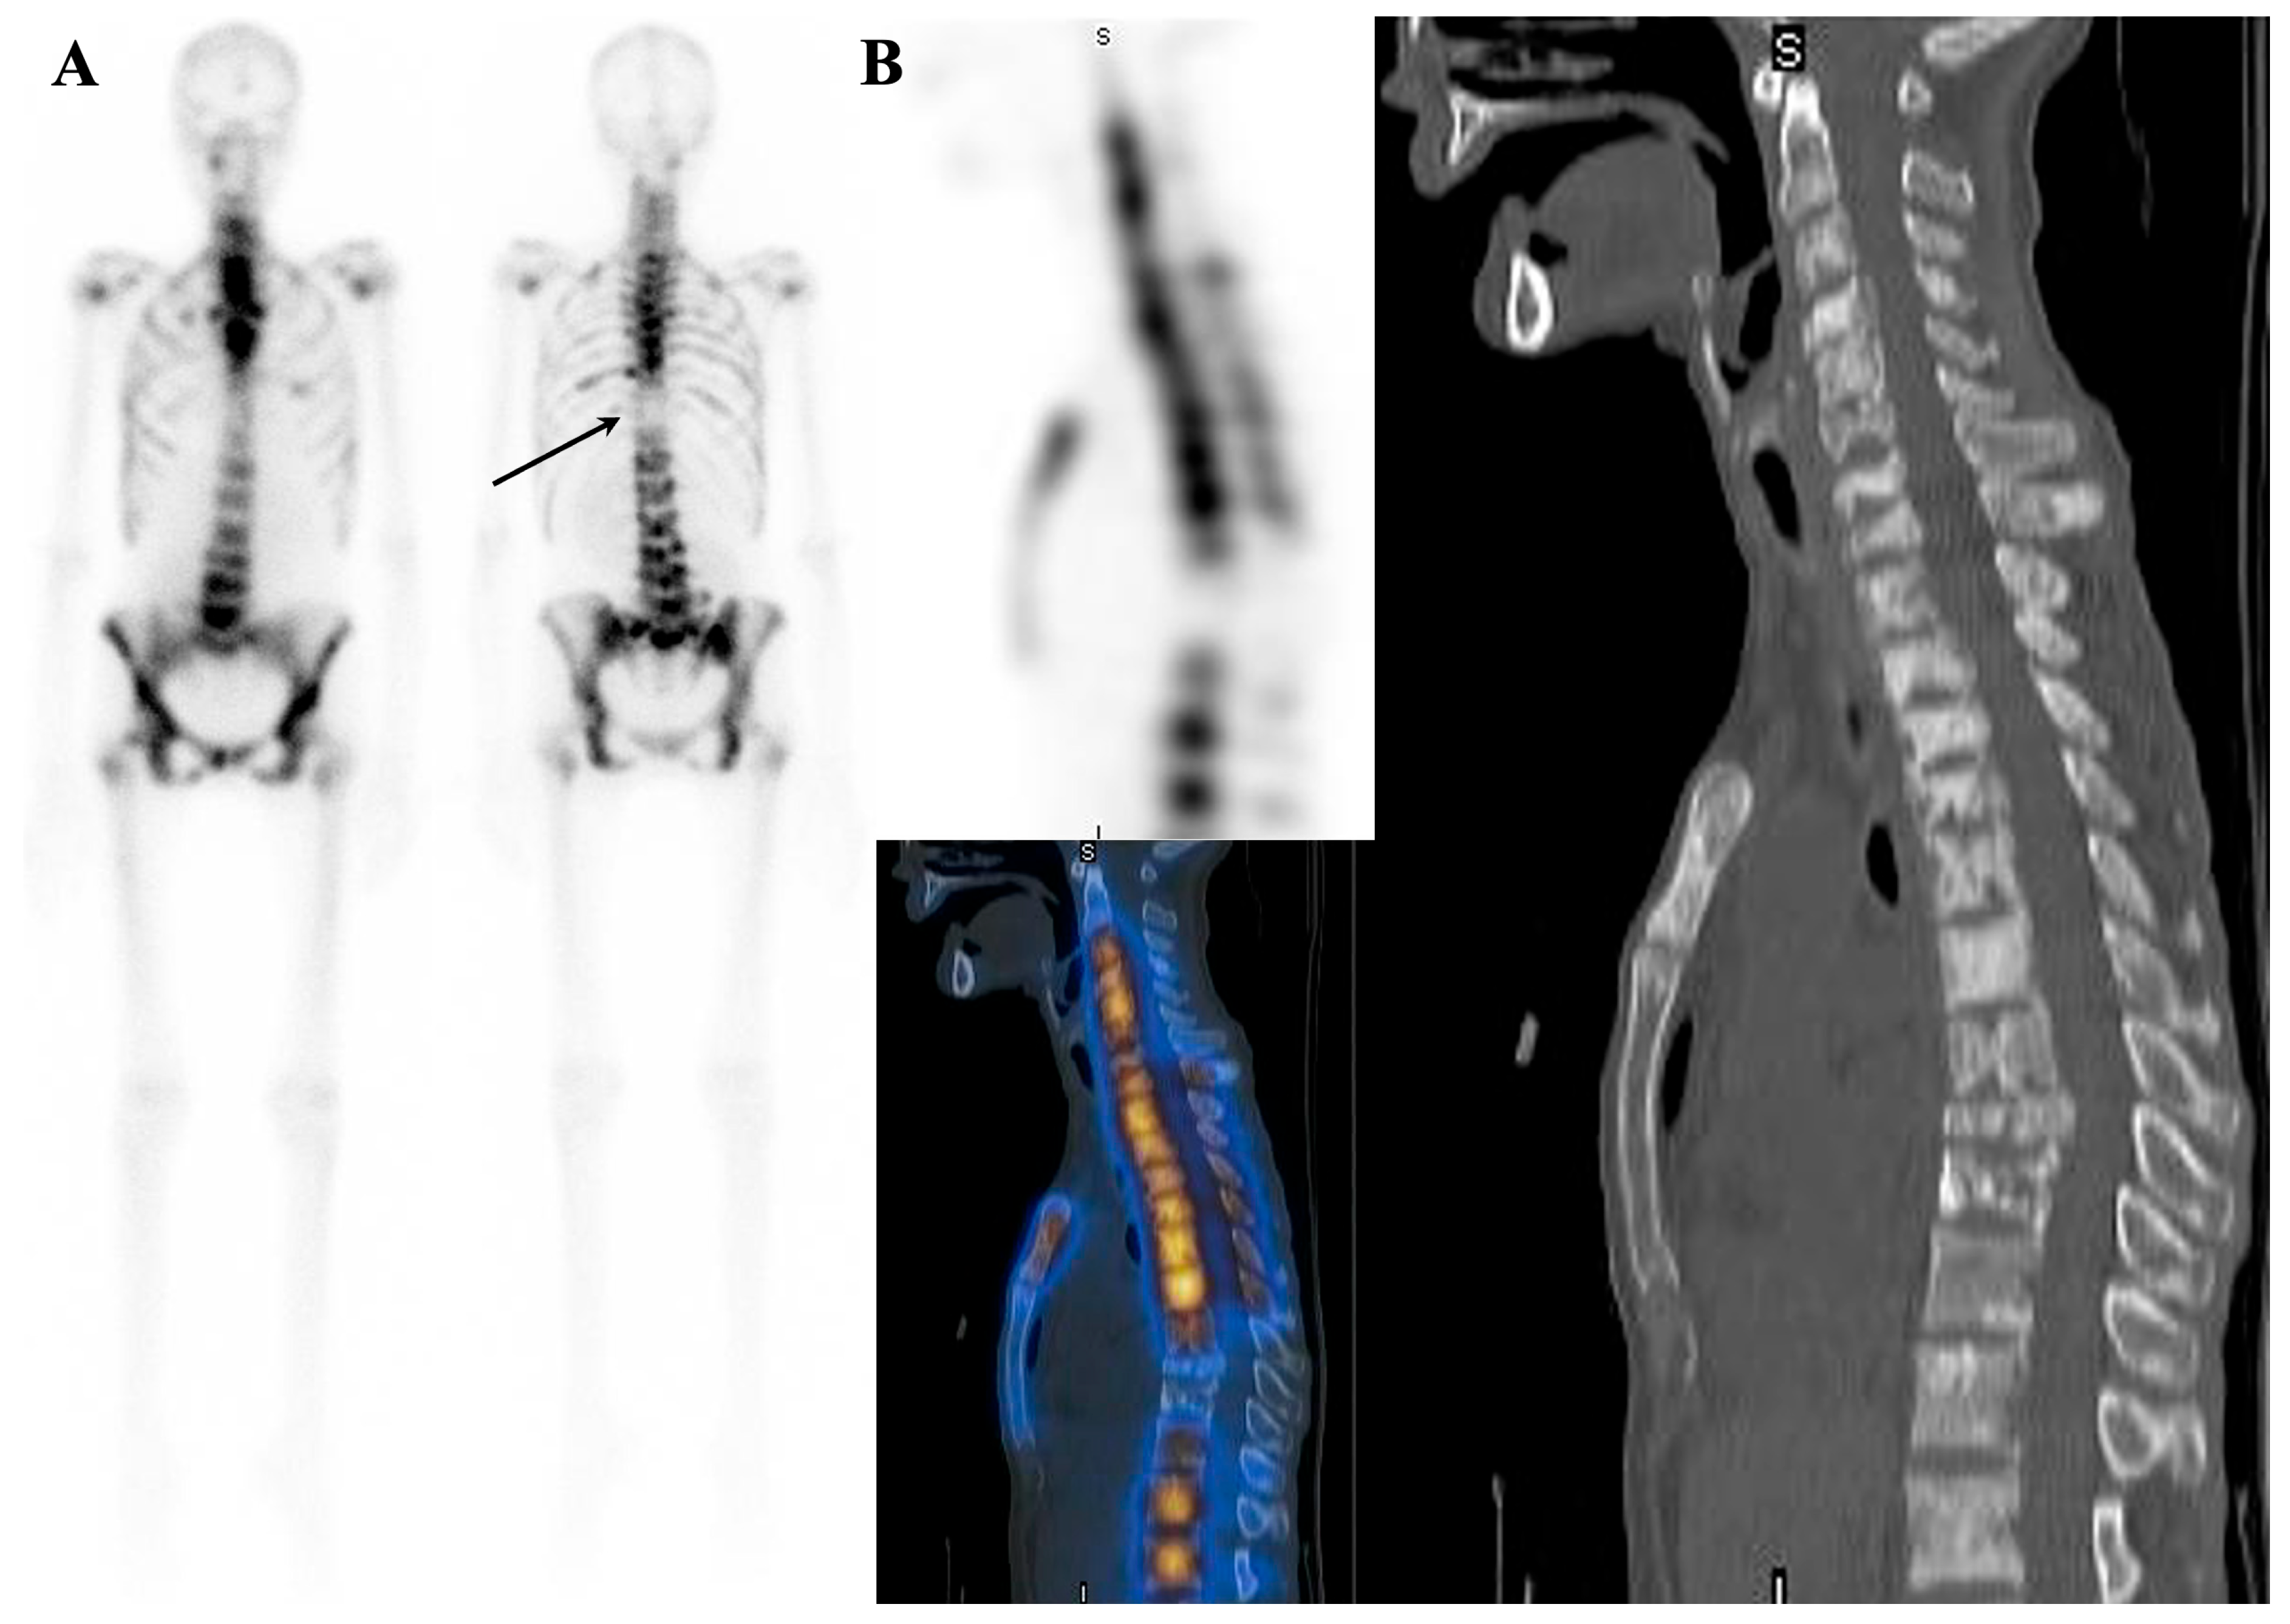

7.1.2. Dynamic Changes in Prostate Cancer Patients with Superscan